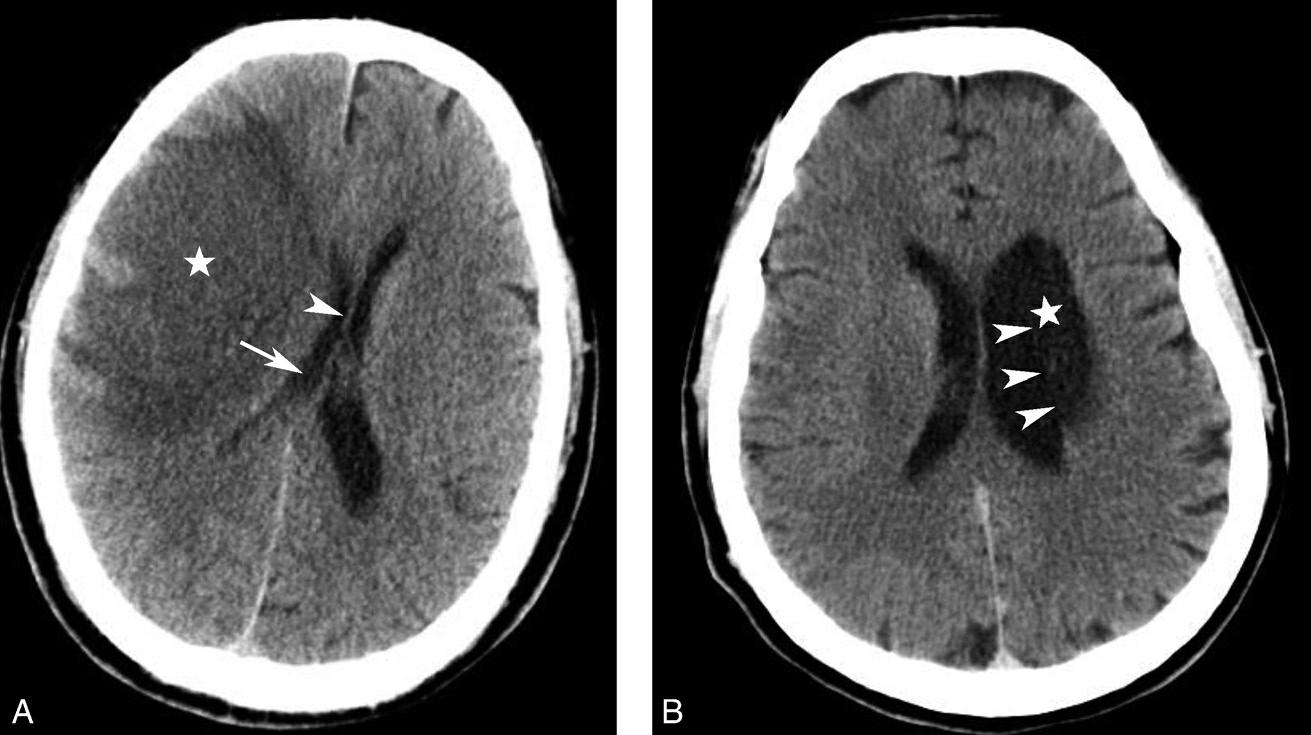

基底节为脑卒中的好发部位,与纹状动脉的解剖特点有关,深穿支动脉的破裂和栓塞可分别引起基底节区的出血和梗死(图1-2-32、图1-2-33)。

图1-2-32 脑出血

A.右侧壳核脑出血,形成高密度血肿(★);B.右侧丘脑出血,呈球形高密度影(箭)

图1-2-33 基底节区脑梗死

A.右侧丘脑梗死,病灶呈圆形低密度影(箭);B.左侧内囊膝部及后肢梗死,呈带状低密度影(箭)